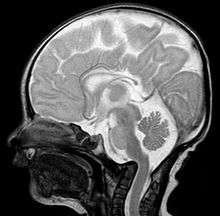

A doctor will base his or her diagnosis on the symptoms the patient has and the results of tests, including:

- Magnetic resonance imaging (MRI), which usually provides the most information